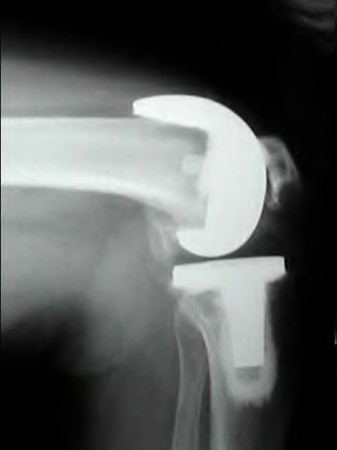

A 45-year-old female with developmental dysplasia of the hip (DDH) presents for THA. Preoperative radiographs show the femoral head is subluxated, with 80% proximal migration relative to the height of the normal true acetabulum. Based on the Crowe classification, what type of dysplasia does she have?

A 35-year-old male presents with right hip pain. MRI confirms avascular necrosis (AVN) of the femoral head. Radiographs show a distinct sclerotic band and cystic changes in the femoral head, but no subchondral collapse or crescent sign. According to the Ficat and Arlet classification, what stage is this, and is core decompression generally indicated?

A patient requires a femoral revision THA for aseptic loosening. Radiographs demonstrate extensive metaphyseal bone loss with the diaphyseal cortical bone remaining fully intact for only 3 cm distal to the tip of the current stem. According to the Paprosky femoral defect classification, what type of defect is present?